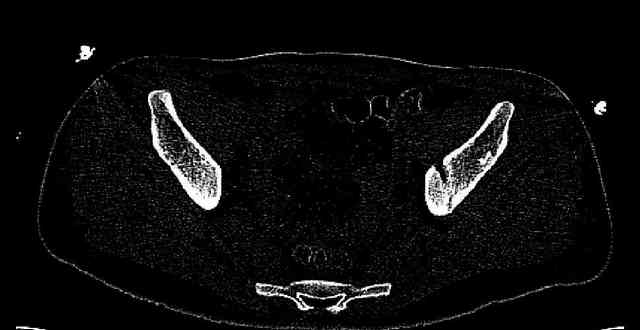

Some more images. Does it help to guess which part of the acetabulum is displaced?

Normal appearing SI joints and a healed posterior column limb... my bet's on caudal segment displacement.

While not claiming to have the best 3D brain around, it appears to me from the limited images available, that the caudal segment is stable from the symphysis to the SI joint on the fracture side. I would love to see the rest of the transverse CT images to see where the fracture line actually exits posteriorly on both the inner and outer tables of the ilium. In my hands,

assuming that the femoral head has followed the cephalad (dome) fragment, I would use an ilioinguinal approach and take down the fracture line from anterior to posterior, distracting with a lamina spreader, if necessary, to clean out and inspect the joint. I would then reduce the cephalad fragment to the caudal fragment using jungbluth or farabeuf clamp and screws and then apply a plate and screws. If the fracture exits posteriorly would you then favor an additional posterior approach to clean out and reduce from that side?